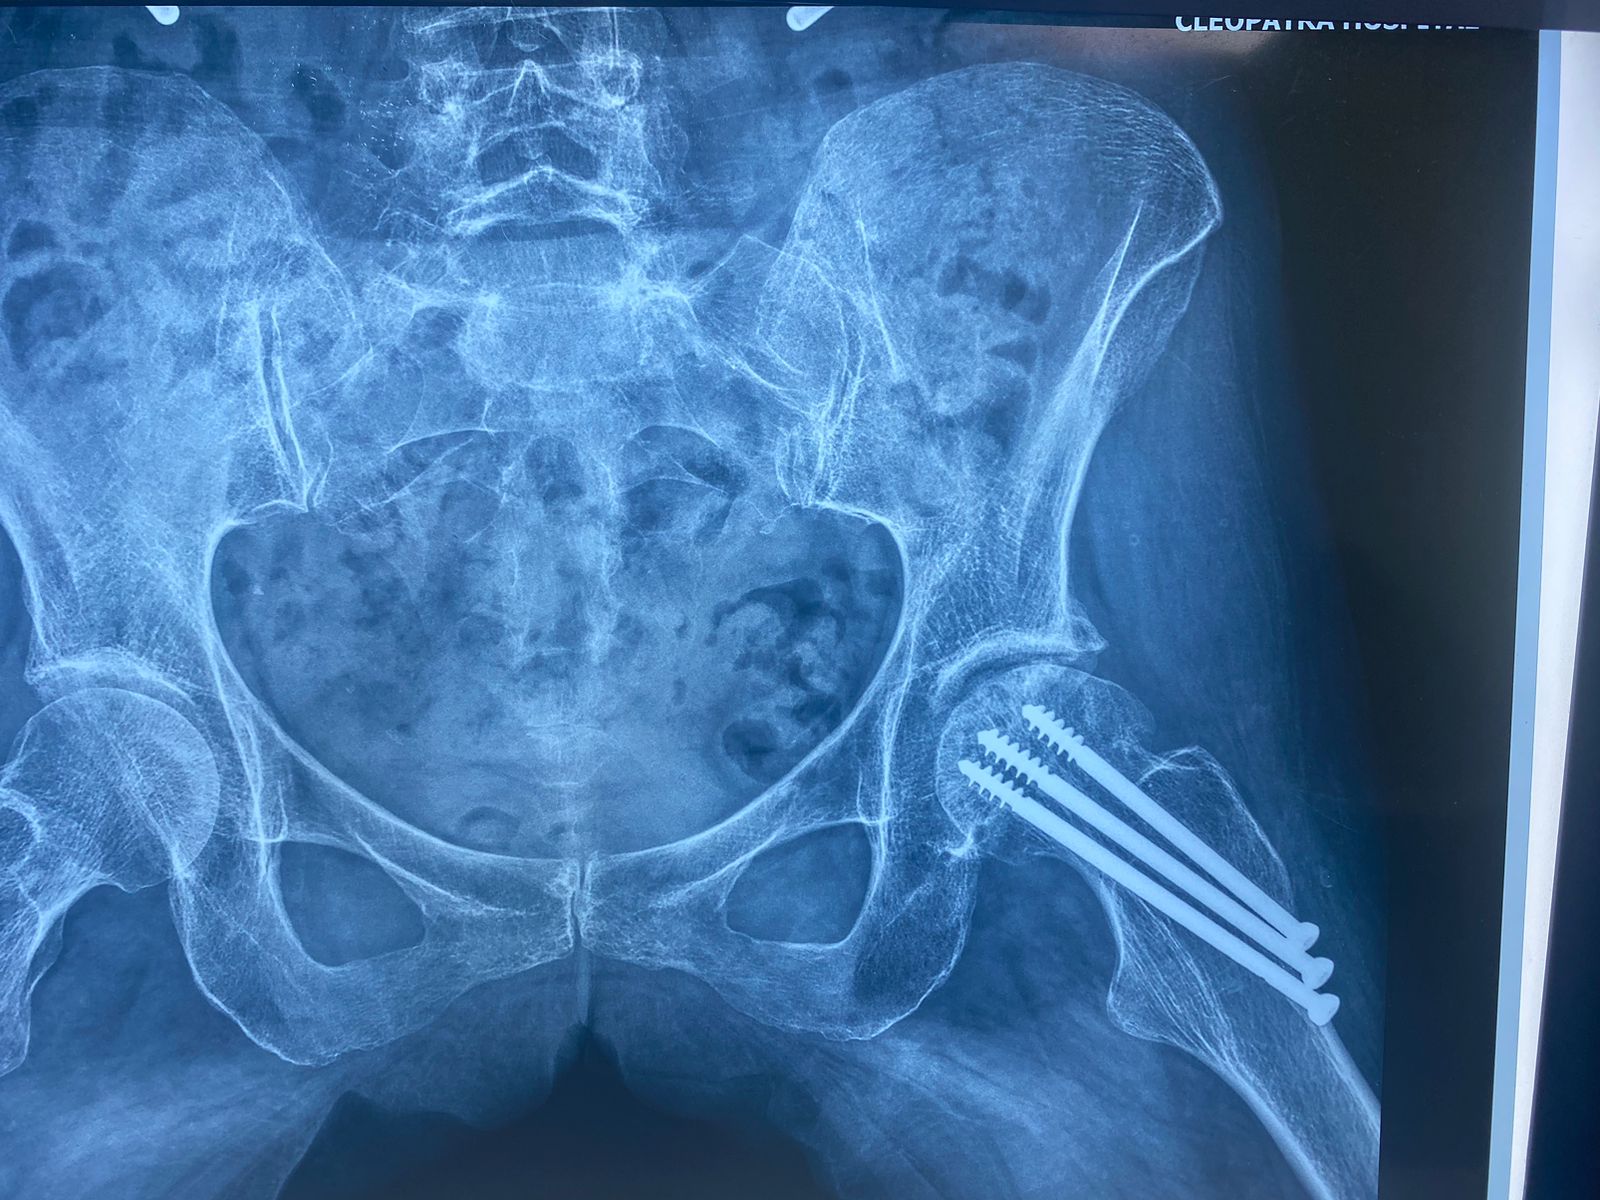

تم إجراء تثبيت داخلي لكسر بالحوض بمسامير عام ٢٠٠٩

في عام ٢٠٢١ بدأت تشعر بالام متزايدة بالمفصل كما بينت الاشعات تآكل به